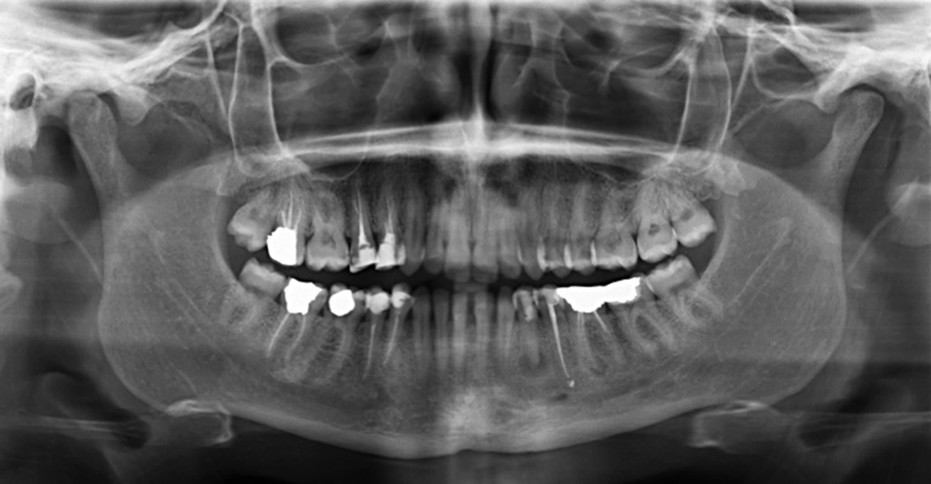

Zdjęcia panoramiczne

Pozwalają na ocenę całego stanu uzębienia oraz innych tkanek narządu żucia. Przedstawiają one wszystkie ważne struktury anatomiczne jak stan i położenie zębów, w tym również zębów zatrzymanych, stawy skroniowo -żuchwowe, dno zatoki szczękowej, budowę kości oraz zmiany zapalne.

Są to zdjęcia przeglądowe, uwidaczniające nieprawidłowości takie jak próchnica zębów, pozostawione po ekstrakcjach korzenie zębów, zęby nieprawidłowo przeleczone kanałowo.

Nasz gabinet posiada aparat cyfrowy, co sprawia że dawka promieniowania jest jeszcze mniejsza.